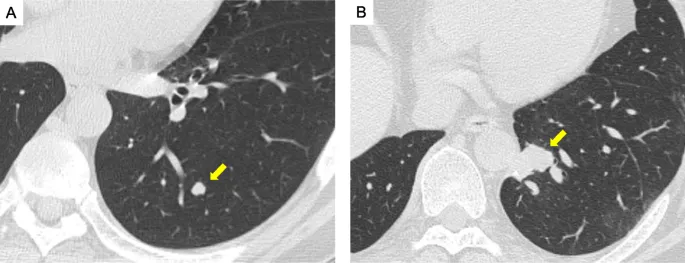

- Lung: Pneumothorax, prolonged air leak.

- Most common for liver (colorectal), lung (sarcoma, CRC), and brain metastases.